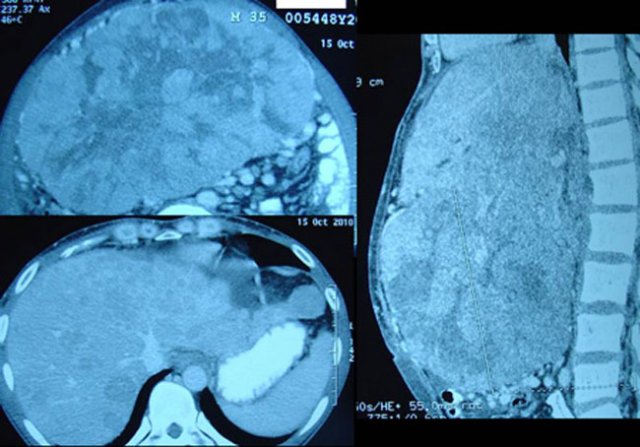

Goh (bukan nama sebenarnya, H438) adalah seorang pria 36 tahun. Pada bulan Juni 2010 ia mengalami diare. Tekanan darahnya rendah. Ia dibawa ke rumah sakit swasta di kota kelahirannya.  USG dilakukan dan dia diberitahu bahwa hatinya tidak baik. Setelah tiga hari dia keluar dari rumah sakit. Kesehatan kembali normal. Dua minggu kemudian perutnya menjadi keras. Dia kembali ke rumah sakit lagi. CT scan dilakukan yang menunjukkan hepatoma – atau kanker hati.

Laporan CT scan tanggal 15 Oktober 2010 menyatakan: “Kedua lobus dari hati yang membesar dan dipenuhi dengan beberapa lesi. Lesi terbesar di segmen 4b ukuran 15 x 20 x 15.6 cm.  Kesimpulan: multicentric hepatoma dengan asites minimal dan melebar kiri saluran intrahepatik.”

Hasil tes darah menunjuk enzim hati yang tinggi. SGOT = 203, SGPT = 56, Alkaline fosfatase = 736 dan Alpha-fetoprotein = 213,73.